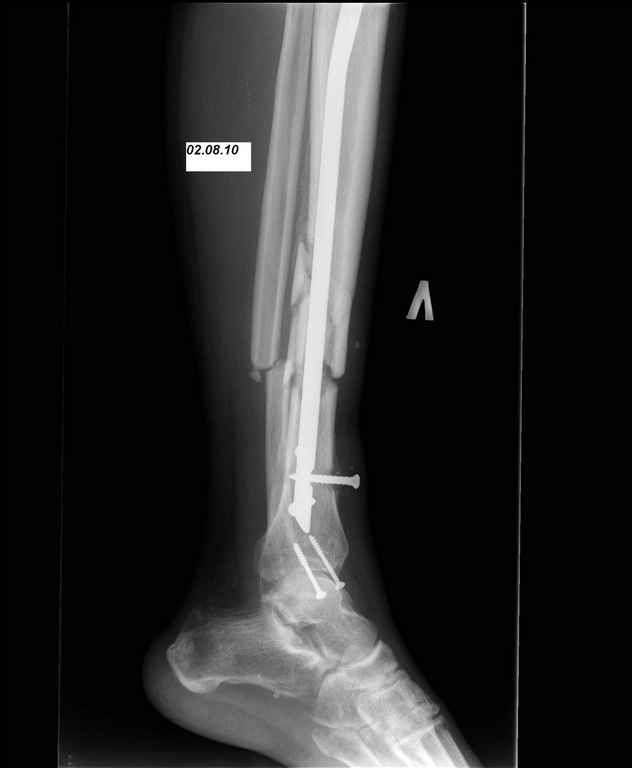

И вот опять объявился. Снимки и фотографии в приложении(первичные потеряны). Около 1 месяца назад появились боли в области нижней трети голени в проекции дистальных блокирующих винтов, передвигался с нагрузкой 50% (сам для себя так решил, сам себе разрешил). Путешествовал по Волгоградской области, обратился к травматологу, со слов перевязывали, лечили антибиотиками. Лучше не стало. Вернулся домой.

Вчера госпитализирован в отделение. Локально умеренный отек, кожная температуа не повышена. По передней поверхности в области дистального блокируюшего винта свищ, скудное гнойное отделяемое, винт удален на перевязке зажимом. «Старый» свищ не функционирует. Взят бак. посев, ждем результат.

добрый вечер,коллеги! поскольку в зоне перелома имеются мелкие отломки, высока вероятность наличия секвестров.(кстати, зону перелома не открывали при остеосинтезе?)Поэтому стоит выполнить полноценный I&D ,а далее либо АВФ либо штифт с АБ. Зависит от размера дефекта после возможной резекции кости (решите интраоперационно)

Однозначно нестабильность.

Во первых штифт тонкий, во вторых коротккий. Не смотря на то что дистальное блокирование выполнено 3 винтами, связь с коротким дистальным отломком получиласть слабоватая если учесть активный образ жизни пациента и его "ненадежность" как выразился Александ Николаевич.

Инфекция в зоне перелома "07.04.10 (S. aureus, чувствительный ко всему что у нас есть)" - это вторичный фактор. Если бы штифт был стабильным, обострения вероятнее всего не было бы.